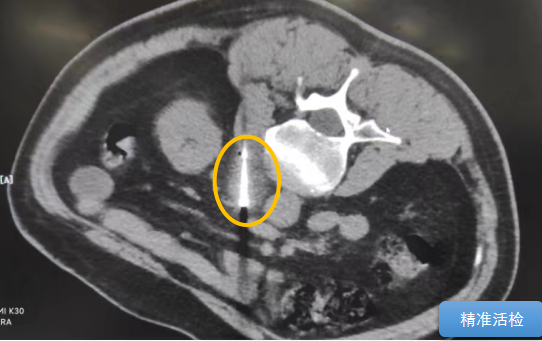

經(jīng)過(guò)多學(xué)科討論,陳寶瑩主任根據(jù)影像資料指出,患者轉(zhuǎn)移瘤位于腹膜后,內(nèi)側(cè)瀕臨人體最大的血管——主動(dòng)脈;前方同樣有血管緊貼腫瘤;外側(cè)是腎臟,后方是椎體和神經(jīng),夾縫中進(jìn)針難度大,治療時(shí)要避免周圍重要臟器、血管和神經(jīng)的損傷,因此可以選擇CT引導(dǎo)下精準(zhǔn)穿刺活檢同步冷凍消融治療,即獲得病理組織有利于下一步全身治療方案的調(diào)整,同時(shí)殺死腹膜后轉(zhuǎn)移瘤,周圍正常組織損傷的可能性也小。

術(shù)中陳寶瑩主任、李鐵柱教授、兀云飛醫(yī)生、魏東紅技師、汝平護(hù)士協(xié)調(diào)配合,夾縫進(jìn)針難度雖大,但在CT引導(dǎo)下逐步進(jìn)針,精準(zhǔn)到位,順利活檢取得組織,由于腫瘤較大,為了提高消融效率,平行置入兩根冷凍消融針,同時(shí)啟動(dòng)冷凍消融,術(shù)中清晰觀察到冰球完全覆蓋病變,患者沒(méi)有任何不舒服,治療中還可以和醫(yī)生聊天。